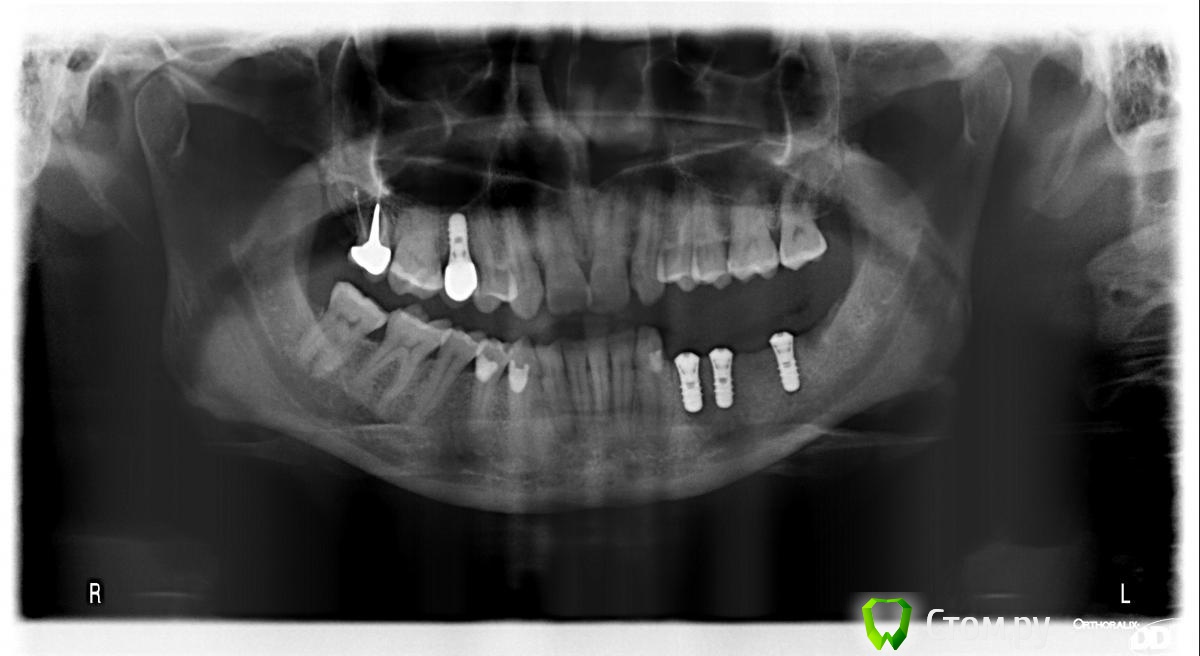

mapmax Опубликовано 3 марта, 2014 Поделиться Опубликовано 3 марта, 2014 Итак,коллеги,нуждаюсь в Вашем совете. У пациентки концевой дефект в обл 34 35 36 37, в периапикальной обл. 34 был воспалительный процесс который обострился и осенью прошлого года зуб был удален(не мной). Сейчас стоим перед имплантацией. Я рекомендую ставить импланты в обл отсутствующих зубов,но по финансовым соображениям пациентка настаивает на операции в обл 34 35 и позже в обл 36 37. Система выбрана Штрауманн SP SLActiv. Из за особенностей формы альвеолярного отростка в обл. 34 35( S-образная) и недавнего удаления 34 я рассматриваю установку импланта с язычным наклоном размера 4.8х10 RN в обл 35 RN 4.8х12. Но есть опасность оголения витков с вестибулярной стороны.Может все же сперва провести аугментацию "Аллопластом" с мембраной с вестибулярной стороны и отсрочено имплантация?! Срезы ДКТ прилагаю. Спасибо. Ссылка на комментарий

mapmax Опубликовано 19 марта, 2014 Автор Поделиться Опубликовано 19 марта, 2014 (изменено) вот оптг. сегодня пациент был на осмотре-отек незначительно сохраняется, но дела идут на поправку. Изменено 19 марта, 2014 пользователем mapmax Ссылка на комментарий